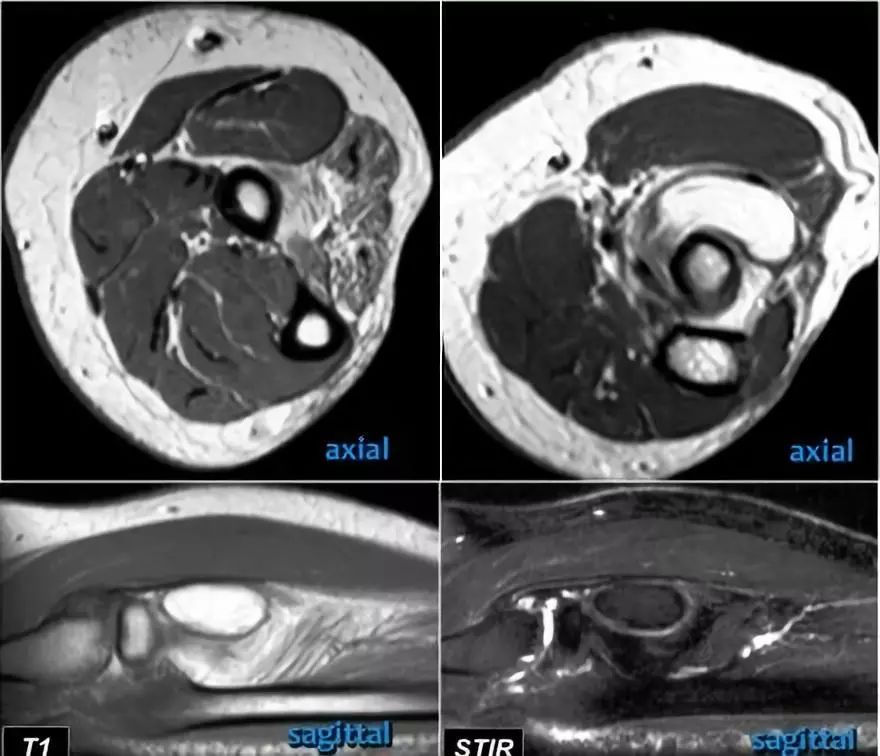

下面这是另一个例子。在T1W图像上有一些增厚和一些中间信号。这可能是肌腱变性,但总是看T2W图像寻找撕裂。在这种情况下,有部分撕裂。

下面是另一种情况。在矢状图像上,我们不确定可能的撕裂。也许只有一些肌腱炎或肌腱炎。轴向图像显示部分撕裂(红色箭头)。

始终确保你的轴向扫描一直到结节,因为你太早停止,就像在这种情况下,你只会看到增厚的肌腱和一些液体,但你不确定可能的撕裂。